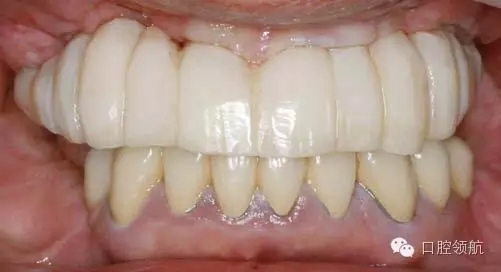

首先確認(rèn)是否有炎癥表現(xiàn),結(jié)果是沒有問題(圖1)。

圖1 戴入種植體支持的上頜全口整體連接的臨時上部結(jié)構(gòu)。1周后來院時訴前頭部有勒緊樣疼痛。